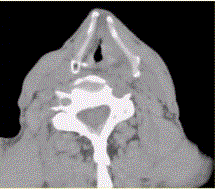

问题 患者男,60岁,声音嘶哑半年,CT表现如下图。 有关喉癌,正确的表述是

选项 A.喉癌以鳞癌多见 B.声门上区淋巴结转移最常见,声门下区次之 C.声门区喉癌好发于声带后1/3与中1/3的交界处 D.喉癌诊断中最重要的内容之一为评价前联合有无受累 E.CT仿真内镜可清晰显示声门区病变 F.喉癌以腺癌多见

答案 ABDE